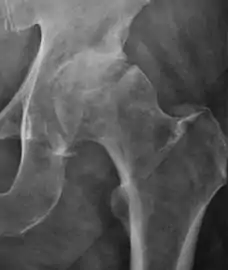

Plain radiography allows us to categorize the hip as normal or dysplastic or with impingement signs (pincer, cam, or a combination of both). Besides these, pathologic processes like osteoarthritis, inflammatory diseases, infection, or tumors can also be identified (Figure 1).[1]

Figure 1.

- Osteoarthritis

In adults, one of the main indications for radiographs is the detection of osteoarthritic changes (Figure 1(e)). Nevertheless, radiographs usually detect advanced osteoarthritis that can be graded according to the Tönnis classifications. The grading system ranges from 0 to 3, where 0 shows no sign of osteoarthritis. Intermediate grade 1 shows mild sclerosis of the head and acetabulum, slight joint space narrowing, and marginal osteophyte lipping. Grade 2 presents with small cysts in the femoral head or acetabulum, moderate joint space narrowing, and moderate loss of sphericity of the femoral head. Grade 3 is the severest form of osteoarthritis, which manifests as severe narrowing of the joint space, large subchondral cyst with productive bone changes that may lead to deformity of the bone components of the joint, while secondary osteoarthritis due to calcium pyrophosphate deposition can be diagnosed when calcification of hyaline cartilage and fibrocartilage is detected.[1]

There are other pathological conditions that can affect the hip joint and radiographs help to make the appropriate diagnosis. Acute bacterial septic arthritis can be diagnosed by radiographs when a fast regional osteoporosis and destructive monoarticular process develops (Figure 1(f)). In case of tuberculous or brucella arthritis it is manifested as a slow progressive process, and diagnosis may be delayed.[1]